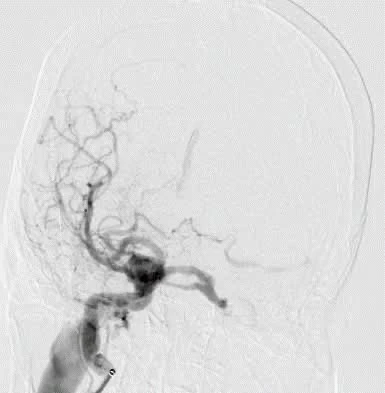

Bệnh nhân được chẩn đoán bị rò động mạch cảnh – xoang hang. Ảnh: BVCC

Theo các bác sĩ, đây là hiện tượng xuất hiện lỗ rò động tĩnh mạch giữa động mạch cảnh và xoang hang, khiến thay đổi các dòng dẫn lưu máu tại xoang hang.

Bệnh nhân N được chỉ định can thiệp nội mạch – phương pháp điều trị phổ biến và hiệu quả nhất hiện nay. Thủ thuật sử dụng vòng xoắn kim loại (coil) để bít tắc đường rò bất thường, khôi phục lưu thông máu bình thường trong hệ tuần hoàn não.